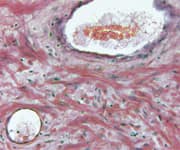

Neither technique, of course, provides information about the potential severity or extent of any tumor found. To get that evidence, doctors turn to an ultrasound procedure, typically followed by a needle biopsy (tissue sampling) under ultrasound guidance.

The most common approach is called transrectal ultrasound biopsy. The main problem with this technique is that it’s inadequate for assuring that all of the tumor will be detected, and misses up to 46% of significant (high-grade) cancers.7,12 Studies have shown that transrectal ultrasound biopsies bear little resemblance to the actual pathological findings when the entire gland is removed, which clearly indicates room for improvement.12,13

Numerous sources suggest that the use of multiparametric MRI is useful for identifying and locating significant cancer in the prostate. While indications suggest that the use of the multiparametric MRI technology is more accurate than a transrectal ultrasound biopsy in the identification of cancer, findings have shown that its sensitivity for picking up clinically significant tumors in the peripheral zone (or outer area) of the prostate was 85% and just 62% in the transition zone (or innermost section) of the prostate.14

First, they began using a highly accurate means of examining the prostate gland in three dimensions and obtaining biopsy specimens from the entire bulk of the gland. A technique called three-dimensional prostate mapping biopsy, 3D-PMB, provides more accurate information about a tumor’s extent and location compared with a standard transrectal ultrasound biopsy.12,15

This three-dimensional prostate mapping biopsy is extraordinarily accurate and painless, and it does not involve puncturing the rectal wall. This sterile procedure greatly lowers the chance for life-threatening sepsis and debilitating prostatitis, which are sometimes the result of standard transrectal ultrasound biopsies.